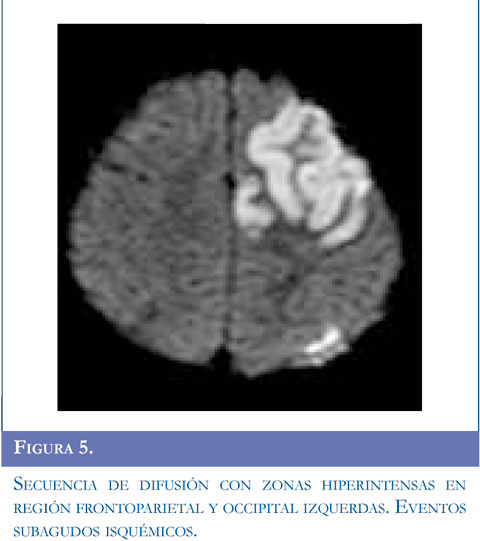

Se inició manejo con carbamazepina, se solicitó RM simple reportada con lesión sugestiva de tipo desmielinizante que compromete sustancia blanca y centros semiovales, sin realce al contraste. Ante la recurrencia de evento de hemiparesia contralateral se realizó RM de control que mostró aumento en el número de las lesiones. Se estudió enfermedad neu-rometabólica con compromiso de sustancia blanca con normalidad en ácidos orgánicos, aminoácidos en orina, acido láctico, ácidos grasos de cadena larga. Presentó nuevo evento de hemiparesia izquierda con estatus convulsivo focal se realizó TAC de cráneo que mostró ACV isquémico parietooccipital derecho, se solicitó panangiografía y doppler carotídeo. Angiografía con compromiso bilateral con hallazgos sugestivos de enfermedad de Moyamoya, y doppler trascraneal hallazgos compatibles con hipoplasia proximal de arterias cerebrales media y anterior izquierda compensado con flujo colateral a través de comunicante posterior izquierda. Valorado por neurocirugía no consideraron manejo quirúrgico. El paciente ha continuado presentando episodios transitorios de ACV. Figuras 4, 5 y 6

Se realizó TAC simple de cráneo que mostró evento isquémico agudo; la resonancia magnética cerebral y la angiografía por RM reportaron lesión vascular isquémica subaguda frontoparietal izquierda cortical, cambios secuelares malácicos subcorticales derechos y gliosis perilesional. Disminución de calibre de las arterias cerebrales medias más evidente del lado derecho, presencia de múltiples estructuras vasculares peri y paraventricular especialmente de lado derecho y comprometiendo región ganglio basal.